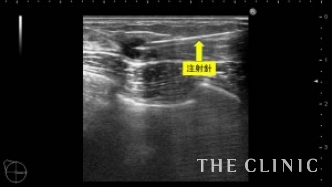

3年前にヒアルロン酸を注入された方です。ヒアルロン酸がしこりになってしまい、見た目・感触ともに無数のしこりが確認出来る状態です。画像は、皮下・乳腺組織内に注入されてしこりになったヒアルロン酸です。

ヒアルロン酸溶解注射を注入して、吸引除去します。

ヒアルロン酸注入によるしこりのエコー診断カルテ